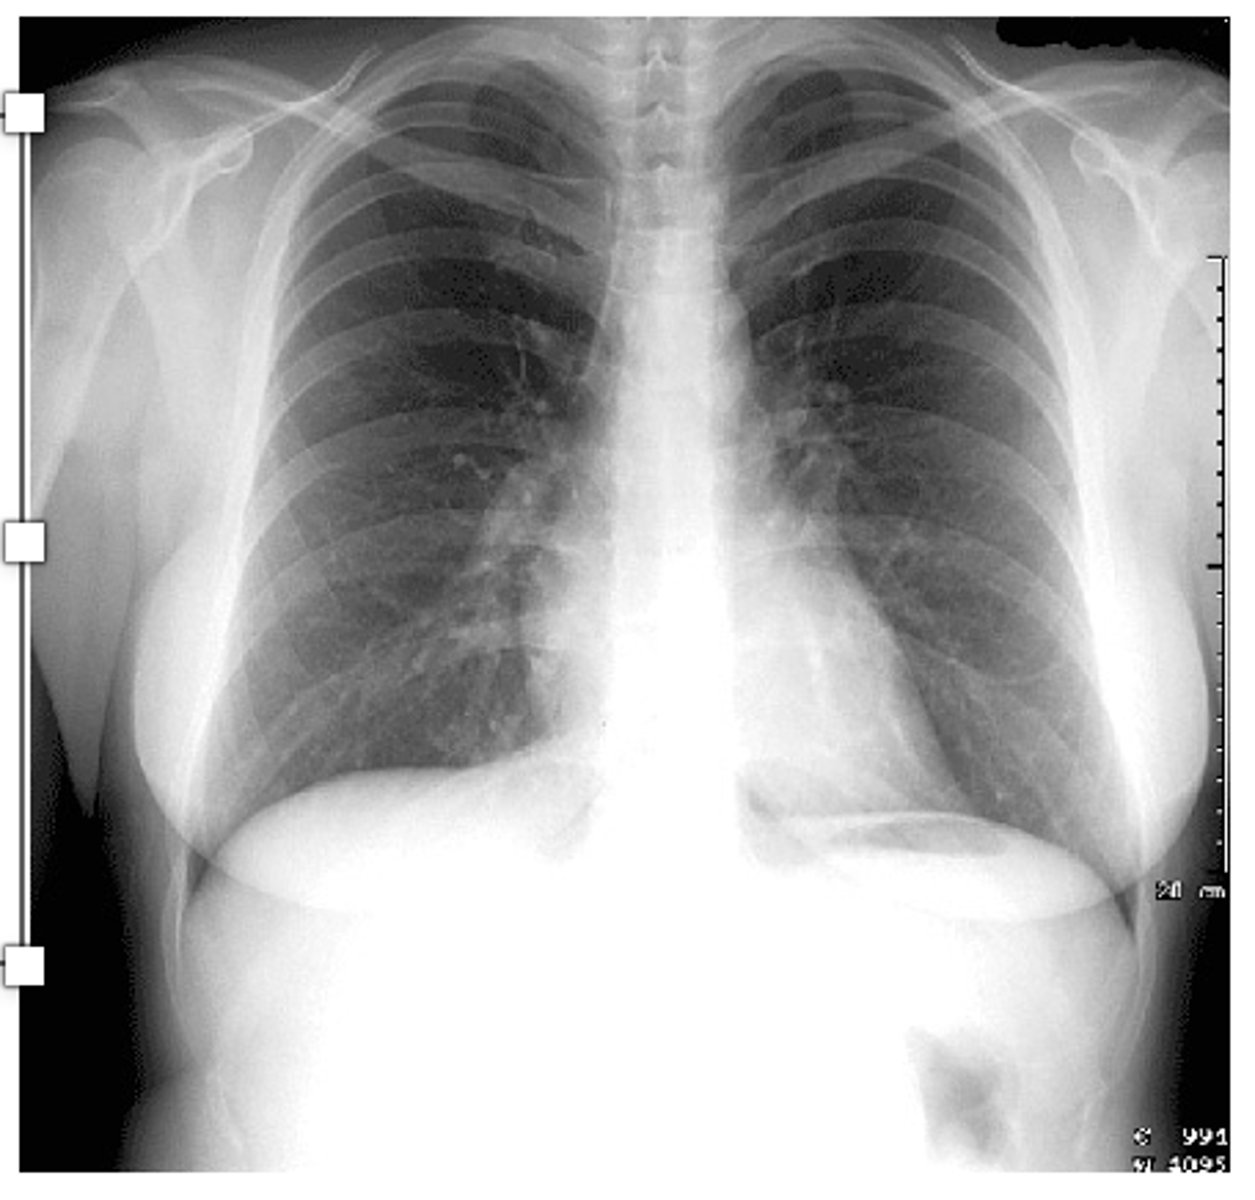

What is always the first step of XRay interpretation?

CONFIRM PT details!! (name, dob, etc)

What does RIPE stand for?

Acronym used to assess image quality

Rotation

• The medial aspect of each clavicle should be

equidistant from the spinous processes. The spinous processes should also be vertically aligned.

•Inspiration

⚬The 5-6 anterior ribs, lung apices, both costophrenic angles and the lateral rib edges should be visible.

•Projection

⚬Note if the film is AP or PA: if there is no label, then assume it’s a PA film

⚬PA = XR beam is posterior (patient’s back)

XR film is anterior (patient’s chest)

⚬AP = XR beam is anterior (patient’s chest)

XR film is posterior (patient’s back)

•Exposure)

⚬The left hemidiaphragm should be visible to the spine, and the vertebrae should be visible behind the heart.

What does ABCDE stand for?

•Airway:

⚬trachea, carina, bronchi and hilar structures.

•Breathing:

⚬lungs and pleura.

•Cardiac:

⚬heart size and borders.

•Diaphragm:

⚬including assessment of costophrenic angles.

•Everything else:

⚬ mediastinal contours, bones, soft tissues, tubes, valves, pacemakers and